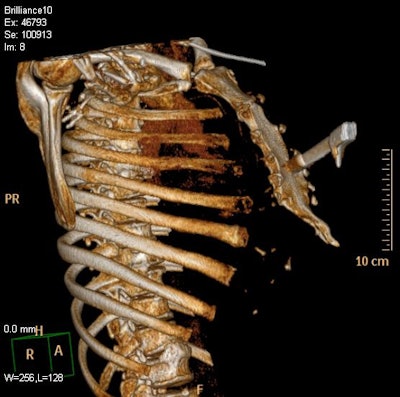

Extremity injuries are by no means a minor injury because force of up to 100 kg/1,000 Newtons can be exerted in a savage attack and can cause severe vascular, soft-tissue, and bony injury requiring expert surgical input from a number of specialist trauma teams and swift imaging to locate size and positioning of weapon, according to Colonel Paul Parker, specialist surgeon in lower limb reconstruction at the Queen Elizabeth Hospital in Birmingham.

Because many stabbing victims die before reaching hospital it is vital the trauma team has as much information about the site of the wound(s) and can arrange to have the radiology team on standby or the use of a mobile machine depending on wound location, weapon, and ease of accessibility. Positioning patients may present a challenge as often the weapon remains in situ until it can be removed in a controlled surgical situation.

In particular, the development of software that allows multiplanar reconstructions has boosted the value of CT.